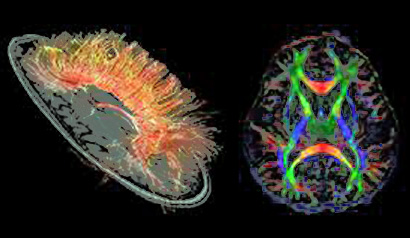

En este sentido, un trabajo publicado en el último número PNAS destaca que lo que nos hace humanos no reside tanto en el lóbulo frontal -la parte que se considera más evolucionada del cerebro, sede de facultades superiores de nuestra especie como la inteligencia- como hasta ahora se pensaba, sino en amplias redes que conectan diversas zonas.

Los autores del trabajo, pertenecientes a las universidades de Durham y Reading argumentan que los lóbulos frontales del cerebro no tienen en nuestra especie un tamaño desproporcionadamente mayor que otras áreas del cerebro y que muchas de nuestras habilidades de alto nivel las llevan a cabo redes más extensas que unen áreas diferentes del cerebro. Y sugieren que puede ser la estructura de estas redes extensas más que el tamaño de cualquier región del cerebro en particular lo fundamental para el funcionamiento cognitivo.

Y proponen una ruta alternativa para la especialización cognitiva basada en la “expansión coordinada de áreas funcionalmente y anatómicamente conectadas, incluyendo regiones corticales y no corticales. El neocórtex, cerebelo y los núcleos intermedios, por ejemplo, muestran una evolución estrechamente correlacionada en términos de número y volumen de neuronas, sugiriendo que la expansión selectiva de los sistemas córtico-cerebelares era una característica general de la evolución del cerebro de los primates”.

“La evolución de las regiones frontales como la corteza prefrontal puede entenderse mejor en términos de su participación en redes más distribuidas. La evidencia experimental implica tales redes distribuidas en las capacidades cognitivas exclusivamente humanas. El lenguaje, por ejemplo, esta soportado por redes distribuidas dentro y fuera de la corteza, incluyendo el cerebelo. Sugerimos que la selección natural amplió tales redes y que fue esto, en lugar del cambio de tamaño más localizado de regiones corticales frontales,  lo que probablemente constituye la base de la especialización cognitiva humana”, concluyen en su artículo.